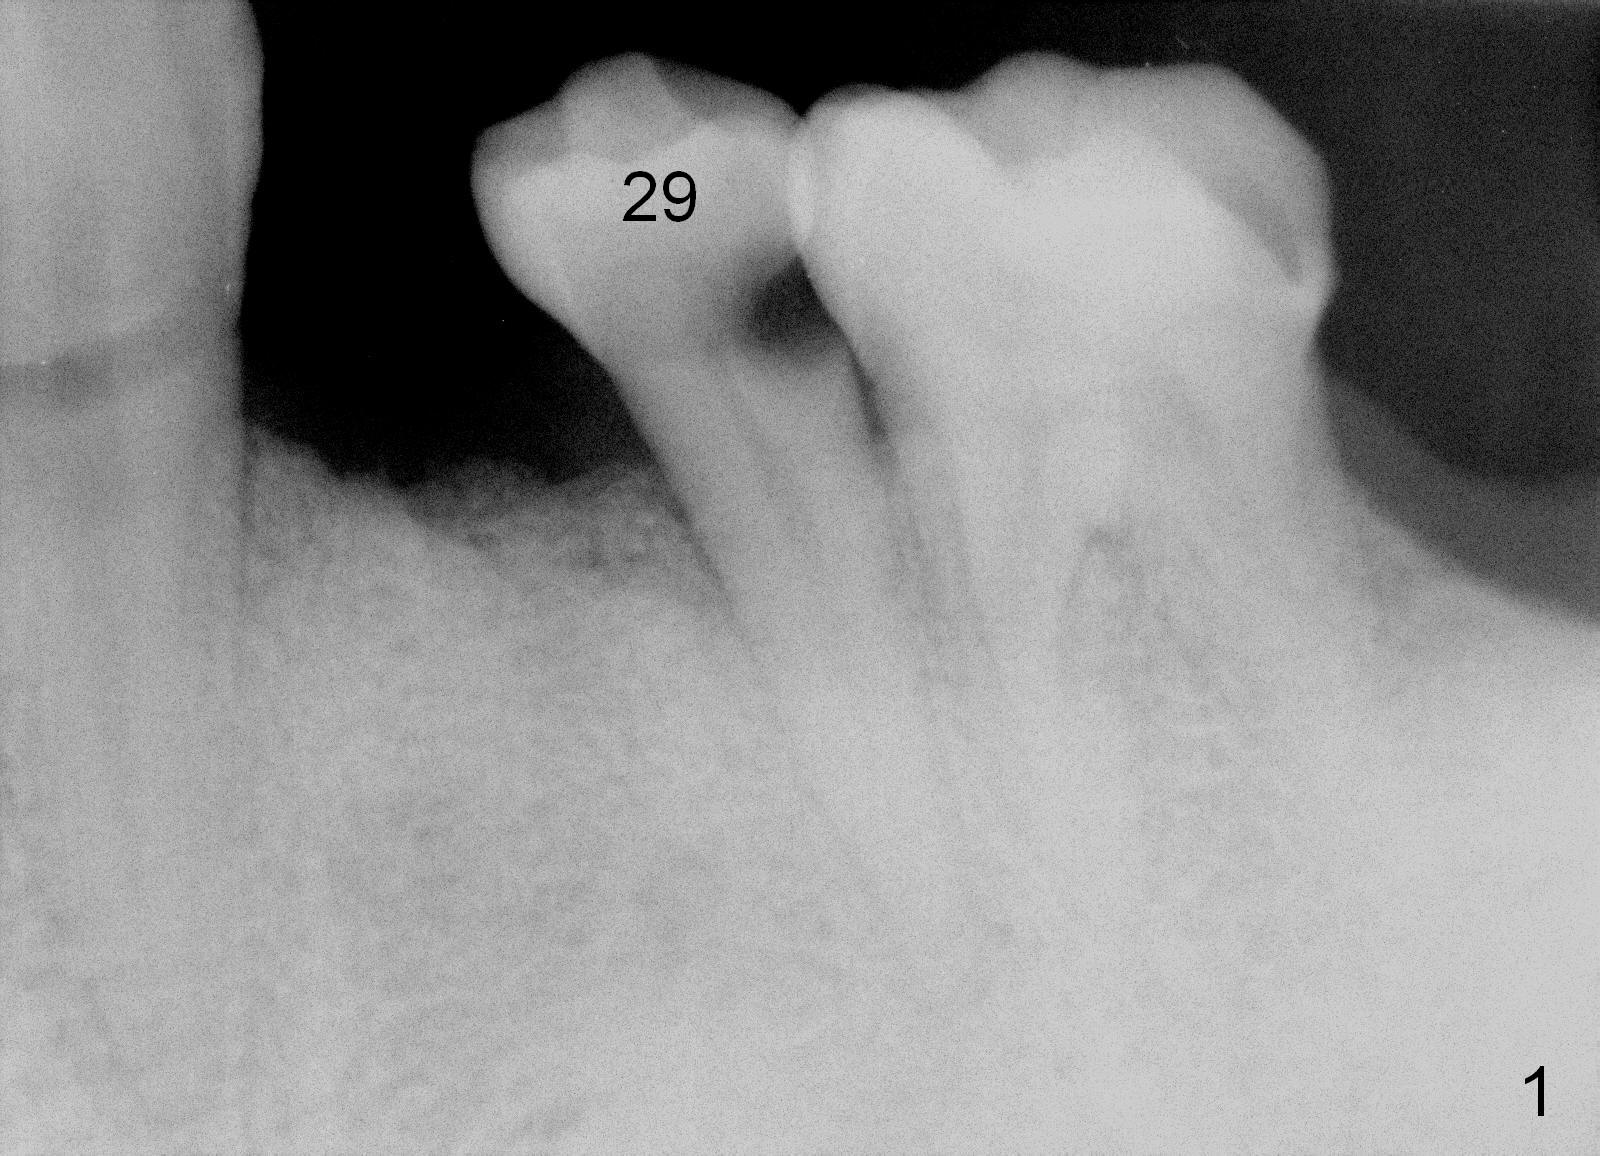

A 56-year-old man has poor dentition (Fig.1). The tooth #20 fractures (not shown) after root canal therapy (Fig.2). A 4.5x14 mm bone-level implant is planned (Fig.3).

CT sagittal section of a similar case shows that the root is also long, but curved (Fig.4). A 4.5x14 mm implant is slightly longer than the root. The apex of the implant has distance to the underlying nerve (N). The coronal section shows that the implant should be placed lingually (Fig.5 L), since the buccal (B) plate is thin (Fig.6 between arrowheads). The first drill (2 mm) is to be placed lingually (Fig.7 red arrow). When the implant is placed, there should be a buccal gap, to be filled with bone graft (Fig.5 red circles).